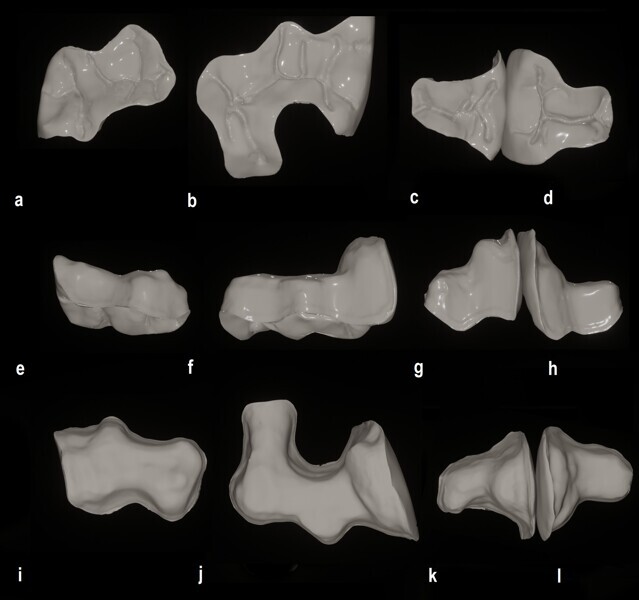

Figs. 24a–l: Virtual restorations from the occlusal view (a–d), buccal view (e–h) and intaglio view (i–l).

The prepared sextant and opposing dentition as well as the occluded arches were scanned with the Medit i900 and the scans imported into Medit ClinicCAD. The restorations were designed in the software with a cement gap of 0.1 mm and a minimum thickness of 0.6 mm to contours matching the preoperative treatment scan (Fig. 23). The virtual restorations were removed from the virtual models in preparation for 3D printing on the Midas printer (Fig. 24). Supports were added to the virtual onlays and the designs prepared for 3D printing.